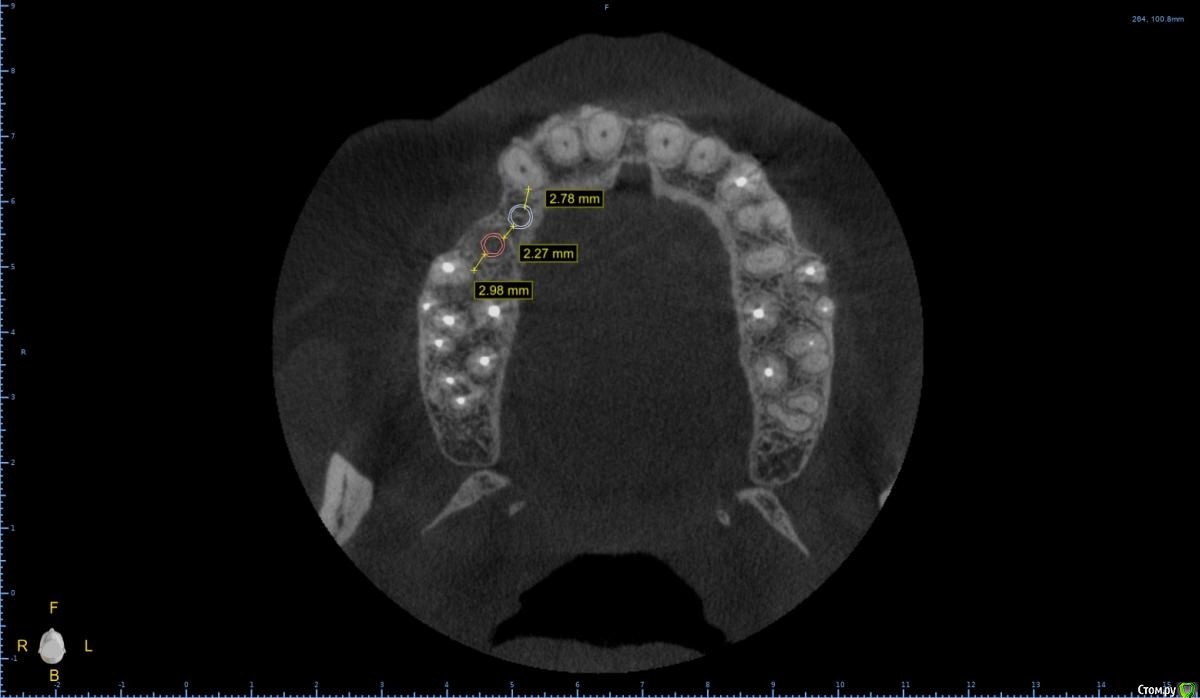

Женька Опубликовано 28 января, 2021 Поделиться Опубликовано 28 января, 2021 Что-то все спрашивают про консоли на имплантатах в области премоляров! Спрошу и я тоже.Коллеги как бы поступили в этом случае?Сам склоняюсь к консоли, но переживаю, что надо бы имплантат пошире, чтобы нагрузку нёс за двоих спокойно. Вариант с двумя винтами не нравится потому как тонковато (не очень) в области 1.4 и необходима редукция около 3мм кости. Ссылка на комментарий

Женька Опубликовано 1 февраля, 2021 Автор Поделиться Опубликовано 1 февраля, 2021 ИМХО два винта, но давайте с замерами тогдаДа, наверное вы правы, два по 3.6 проходят Ссылка на комментарий

Женька Опубликовано 5 февраля, 2021 Автор Поделиться Опубликовано 5 февраля, 2021 Я бы развел винты побольше, лучше ближе к зубам чем друг к другу, кроме того дистальный имплант можно сместить немного небнеекак-то так? 1 Ссылка на комментарий